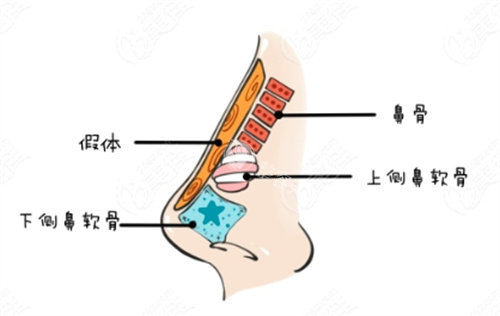

这类问题的核心在于鼻部软骨支撑力不足。传统假体隆鼻虽能垫高鼻背,但对鼻尖塑形结果有限,甚至可能因假体压迫导致鼻头更圆钝。

半肋软骨技术的核心优势在于“材料源于自身,塑形更贴合原生条件”。取用肋软骨中的柔性部分雕刻鼻尖支架,既能避免假体的异物感,又能精细控制鼻尖旋转度、延长鼻小柱。

沧州京美医疗美容鼻子整形术例中,主刀医生采用“悬浮鼻尖”雕刻法:将肋软骨削薄至0.8mm,分层叠加形成弹性支撑结构,术后鼻尖触感柔软,形态微翘而不僵硬。

术例中的姑娘术前鼻头肥厚且皮肤张力较弱,医生特别设计了“双拱形支架”:上方用肋软骨搭建稳固的鼻梁基底,下方通过软骨颗粒填充鼻翼基底,缩小鼻头外扩的同时提升面部立体度。

解剖学精细设计:根据鼻部皮肤厚度、软骨强度定制方案,避免盲目追求高度导致鼻尖发白或穿透;

仿生支架雕刻:肋软骨需保留天然弧度,模拟原生鼻中隔的力学结构;